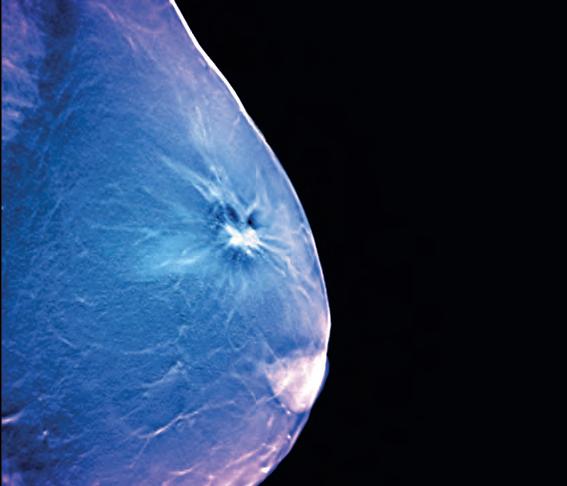

Researchers from the US report that digital breast tomosynthesis (DBT) has improved breast cancer screening performance in community practice and identifies more invasive cancers, when compared with digital mammography.

In addition, radiologists’ interpretive performance improved with DBT, according to the new study.

After gaining US Food and Drug Administration approval in 2011, DBT was rapidly adopted in the US. As of September 2022, 84% of all mammography screening facilities in the US had DBT units.

Public Health England 2021 guidance states that tomosynthesis has been approved for use in the NHS breast screening programme as an optional extra tool in the assessment of screen-detected soft tissue breast abnormalities. However, it must not be used for routine screening outside of a clinical trial approved by the breast screening research advisory committee.

To establish performance benchmarks for DBT screening and evaluate performance trends over time in US community practices, the research team collected DBT screening exams from five Breast Cancer Surveillance Consortium (BCSC) registries between 2011 and 2018.

Performance measures included abnormal interpretation rate, cancer detection rate, sensitivity, specificity and false-negative rate.

Compared to BCSC digital mammography screening exams from the time and previous BCSC and National Mammography Database performance benchmarks, all performance measures were higher for DBT, except sensitivity and falsenegative rate, which were similar to concurrent and prior digital mammography performance measures.

A total of 896,101 women undergoing 2,301,766 screening exams – 458,175 DBT and 1,843,591 2D digital mammography–were included in the retrospective study.

The abnormal interpretation rate was 8.3%, cancer detection rate was 5.8 per 1000 exams, sensitivity was 87.4%, and specificity was 92.2%.

With DBT, assessed radiologists achieved the recommended acceptable performance ranges for cancer detection rate (97.6%), sensitivity (91.8%), abnormal interpretation rate (75.0%) and specificity (74.0%).

“Radiologists appear to perform better with digital breast tomosynthesis and have higher accuracy on screening 3D mammograms than 2D mammograms across US practices,” said lead author Christoph I. Lee, Professor of Radiology at the University of Washington School of Medicine in Seattle. “As this becomes the mainstay screening modality, we hope to see improved screening outcomes for women.”

The results of the study have been published in Radiology, a journal of the Radiological Society of North America (RSNA).